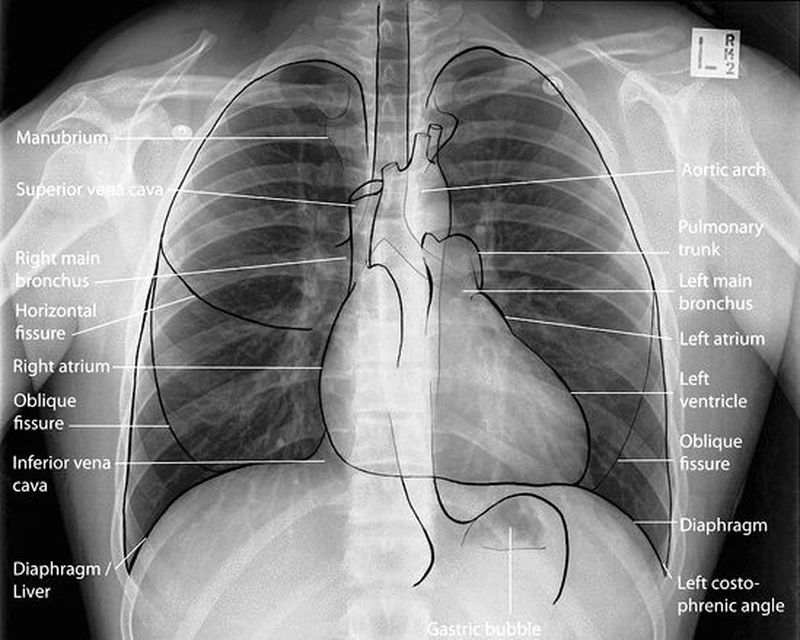

Chest X ray

Anterior view

Radiology

Pulmonology